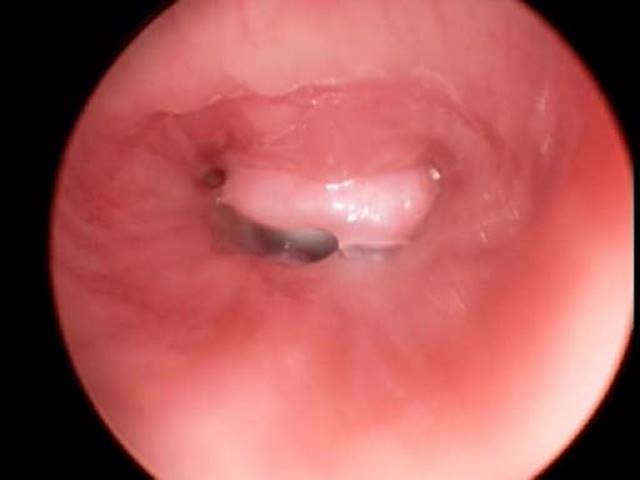

Tracheal mucosal granulation or suprastomal granuloma/fibroma formation is reported in 30 to 40% of children with tracheostomy (Fig. 11.5).22 Granulation tissue refers to the pink, friable healing tissue whereas granulomas/fibromas represent the more thickened and indurated respiratory mucosa. The most common cause of granulation tissue is either trauma at the distal tip of the tracheostomy tube or excessive suctioning. Granulation can lead to bleeding or partial tube occlusion. Suprastomal granuloma, tissue on the anterior tracheal wall proximal to the stomal site, can be problematic when voice is diminished or when decannulation is being attempted. Formation is likely due to several factors, most significantly tube movement and irritation. These lesions can be removed endoscopically using microlaryngeal instruments, lasers, or microdebriders, or they can be excised through the stoma using open techniques.

Figure 11.5 Suprastomal granuloma completely occluding suprastomal airway leading to impaired phonation and inability to decannulate.